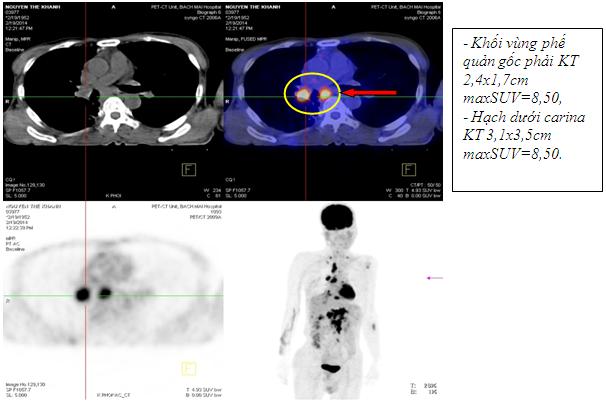

Kết quả chụp PET/CT: Khối vùng phế quản gốc phải KT 2,4x1,7cm; maxSUV=8,50; Hạch dưới carina KT 3,1x3,5cm ; maxSUV=8,50;Nhiều hạch ổ bụng dọc theo ĐMchủ bụng tạo thành khối lớn KT 8,5x5,1cm và 5,1x3,9cm, tăng hấp thu F-18 FDG, maxSUV=10,45; Hạch thượng đòn phải KT 1,1cm, tăng hấp thu F-18 FDG, max SUV=5,67; Hạch thượng đòn trái KT 0,8cm, max SUV=3,97; Tổn thương cung sau xương sườn số 2 bên phải tăng hấp thu F-18 FDG, max SUV=3,13; Nhu mô gan hạ phân thùy VI có nốt KT 1,2cm, tăng hấp thu F-18 FDG, max SUV=4,15.